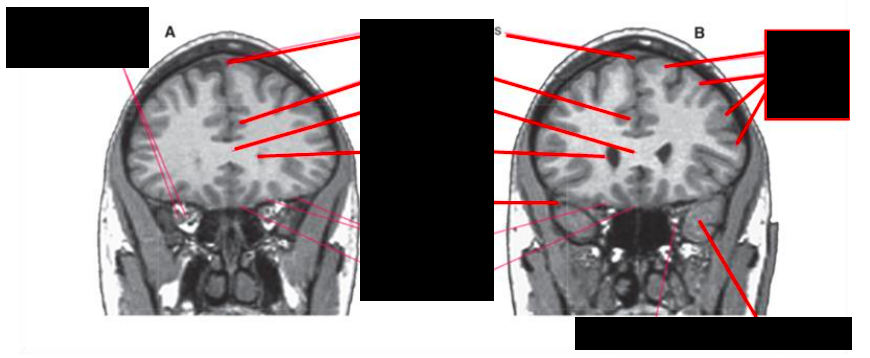

Alzheimers

Large amount of brain degeneration

Enlargement of subarachnoid space, enlarged venticles

Clinical: Possible Disease?

Huntington’s Disease

Loss of volume of Caudate Nucleo, enlargement of frontal horns

Enlargement of subarachnoid space, frontal convexity, interhemispheric scissure, sylvian region, and choroid fissures